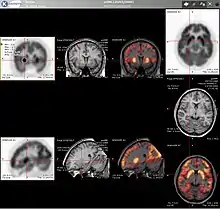

Neurology

PET imaging with oxygen-15 indirectly measures blood flow to the brain. In this method, increased radioactivity signal indicates increased blood flow which is assumed to correlate with increased brain activity. Because of its 2-minute half-life, oxygen-15 must be piped directly from a medical cyclotron for such uses, which is difficult.[16]

PET imaging with FDG takes advantage of the fact that the brain is normally a rapid user of glucose. Standard FDG PET of the brain measures regional glucose use and can be used in neuropathological diagnosis.

Brain pathologies such as Alzheimer's disease (AD) greatly decrease brain metabolism of both glucose and oxygen in tandem. Therefore FDG PET of the brain may also be used to successfully differentiate Alzheimer's disease from other dementing processes, and also to make early diagnoses of Alzheimer's disease. The advantage of FDG PET for these uses is its much wider availability. Some fluorine-18 based radioactive tracers used for Alzheimer's include florbetapir, flutemetamol, Pittsburgh compound B (PiB) and florbetaben, which are all used to detect amyloid-beta plaques, a potential biomarker for Alzheimer's in the brain.[17]

PET imaging with FDG can also be used for localization of "seizure focus". A seizure focus will appear as hypometabolic during an interictal scan.[18] Several radiotracers (i.e. radioligands) have been developed for PET that are ligands for specific neuroreceptor subtypes such as [11C]raclopride, [18F]fallypride and [18F]desmethoxyfallypride for dopamine D2/D3 receptors; [11C]McN5652 and [11C]DASB for serotonin transporters; [18F]mefway for serotonin 5HT1A receptors; and [18F]Nifene for nicotinic acetylcholine receptors or enzyme substrates (e.g. 6-FDOPA for the AADC enzyme). These agents permit the visualization of neuroreceptor pools in the context of a plurality of neuropsychiatric and neurologic illnesses.